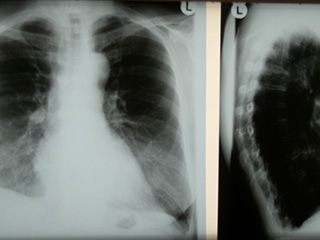

Röntgen

Die Röntgenaufnahme der Brustorgane (Herz, Lunge, Aorta) dient unter anderem dem Nachweis von Herzerkrankungen wie Herzschwäche oder der Vorsorge von Lungentumoren. Sie ist eine Standarduntersuchung und durch Hartstrahlentechnik mit einer nur sehr geringen Strahlenbelastung verbunden.